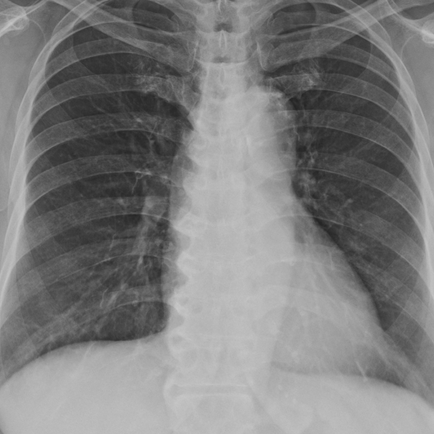

후비루에 의한 기침의 배경에서 발생한 발한? 폐렴을 소견/증거는 없어 증상적 투약 후 추적 - 동대문구 답십리, 전농동, 우리안애 우리안愛 내과

호흡기

2025년 1월 27일

1분 분량

미열이 있는 고령의 폐렴, 폐포음의 위치와 흉부촬영과 비교 (2) - 동대문구 답십리, 전농동, 우리안애 우리안愛 내과

2025년 1월 26일

2분 분량

발열은 없는 고령의 폐렴, 폐포음의 위치와 흉부촬영과 비교 - 동대문구 답십리, 전농동, 우리안애 우리안愛 내과

독감과 거의 동시에 중복된 세균성 폐렴 동반; 임상적 호전 및 흉부 추적 - 동대문구 답십리, 전농동, 우리안애 우리안愛 내과